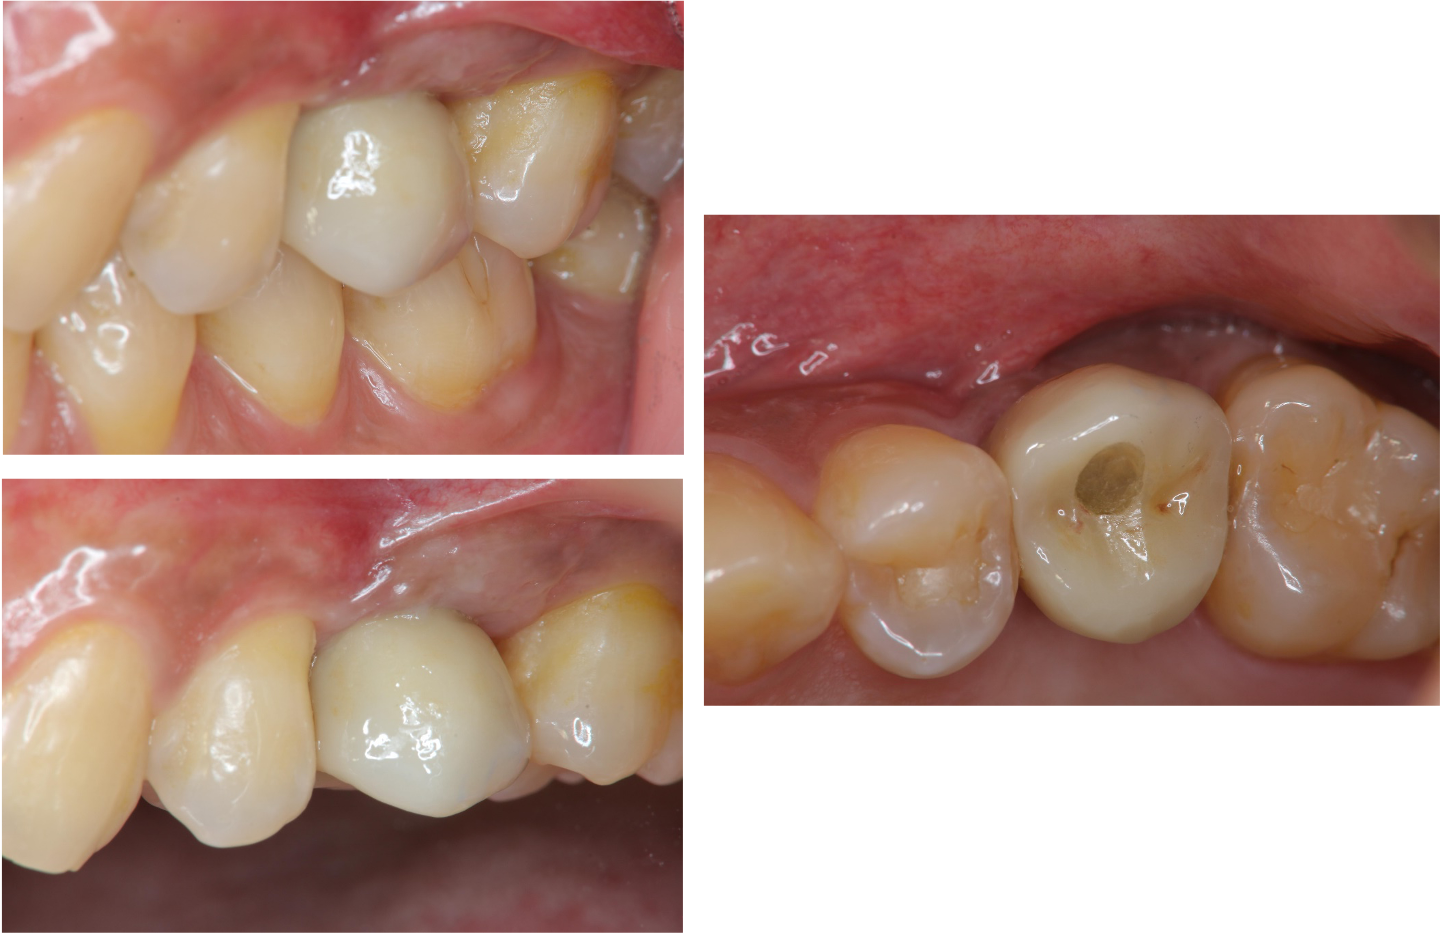

螺絲固位式牙橋

治療後口內照